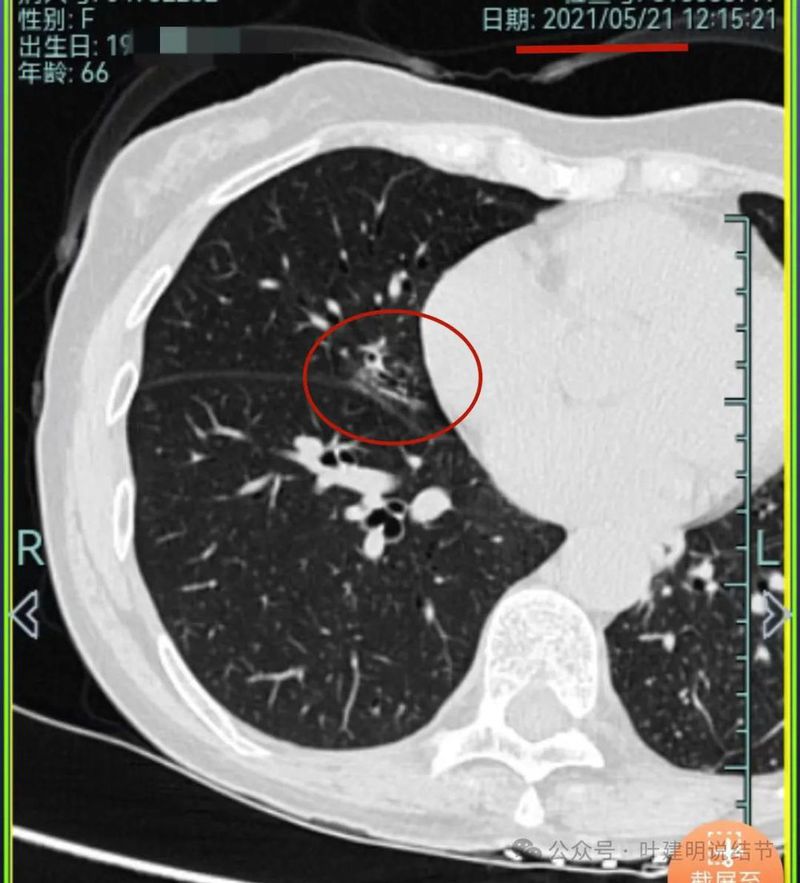

再看2021年随访的影像:

病灶5较前密度略显杂乱,整体密度应该有所增高。

病灶5较前密度又有增高,贴着叶间裂,整体轮廓显得较之前清楚些,更符合恶性表现了,而且应该是浸润性腺癌。

病灶5实性成分明显较前增多明显,总体上有进展,但这个病灶主要周围比较散,显得有些模糊。

我想我们这样也来考虑问题:1、左侧已经手术的确诊是肿瘤性质,左上已经消融的也是随访持续存在的磨玻璃密度结节,虽然没有病理依据,仍然要考虑广义上来讲的肿瘤范畴,看了以前的片子,从2019年到2023年并没有显著的进展,大概是肺泡上皮不典型增生可能性大。右侧的也有磨玻璃结节与混合磨玻璃结节考虑是肿瘤范畴的。所以总体上两肺多原发早期以磨玻璃为表现的肺癌,整体风险都不大。2019年切除的左肺下叶病灶也是纯磨玻璃密度,其实如果继续随访或者只做楔形切除也并没有什么关系。这说明体质本身或者致病的因素,就是容易长磨玻璃肺癌的,即便把目前发现的都解决,后续仍可能再有新的。原因不明,致病因素仍在。2、右肺上叶红色之处从2019年开始,是逐渐进展的,当然即便是现在,也不是说危险就已经很大,考虑仍然是原位癌或者微浸润性腺癌可能性大;中叶蓝色这处乍一看像至少是微浸润,但前后对比以后发现从2019年到现在,几乎没有显著进展,这样的话慢性炎伴肺泡上皮增生或者伴纤维增生也是有可能的,至少风险并不能认为大;右肺下叶黄色这一处,使纯磨玻璃密度,整体轮廓与边界清楚,考虑是肿瘤范畴的,不典型增生可能性较大,也有可能原位癌,随访稍有进展,风险仍然不大;中叶绿色这处是慢性炎伴钙化的,靠近叶裂的地方也像慢性炎,但此处随访有所进展。不过因为有卫星灶,整体显得比较散,所以虽然恶性可能性较大,但也不能完全除外炎性的可能性。当然如果此灶确实恶性,那风险则相对较其他进展缓慢的要高一些。从目前右侧所在的这些病灶来讲,真正有一定的风险而且最为确切的是红色这处,而且应该也没有到浸润性腺癌或者说不处理会要转移很危险这种程度。3、明确了多原发早期肺癌没有办法预防与控制,也明白了目前已经存在的较明显的这些病灶总体风险的高低。我们再来考虑需不需要近期干预处理。左侧既手术过又消融过,右侧的多发病灶目前又还没有到危险很高的程度,又没有办法预防后续再有新的病灶。我个人偏保守,我觉得仍然可以半年复查随访,如果最具风险的病灶有进展并且不处理可能导致不良后果,到这样的程度再来考虑综合如何处理干预便可。4、假如右侧我们予以处理,上叶红色的以及中叶蓝色的都可以楔切,但绿色考虑良性的再进展或以后像恶性时怎么办?而若中叶切除加上叶楔切,在左侧已经手术过的情况下肺功能影响相对也不小,何况右下比较中间的位置还有桔色这处呢。当然右下这处得考虑消融。所以,我的想法还是能熬再熬下,待其他监测有变化再通盘考虑。意见供参考!